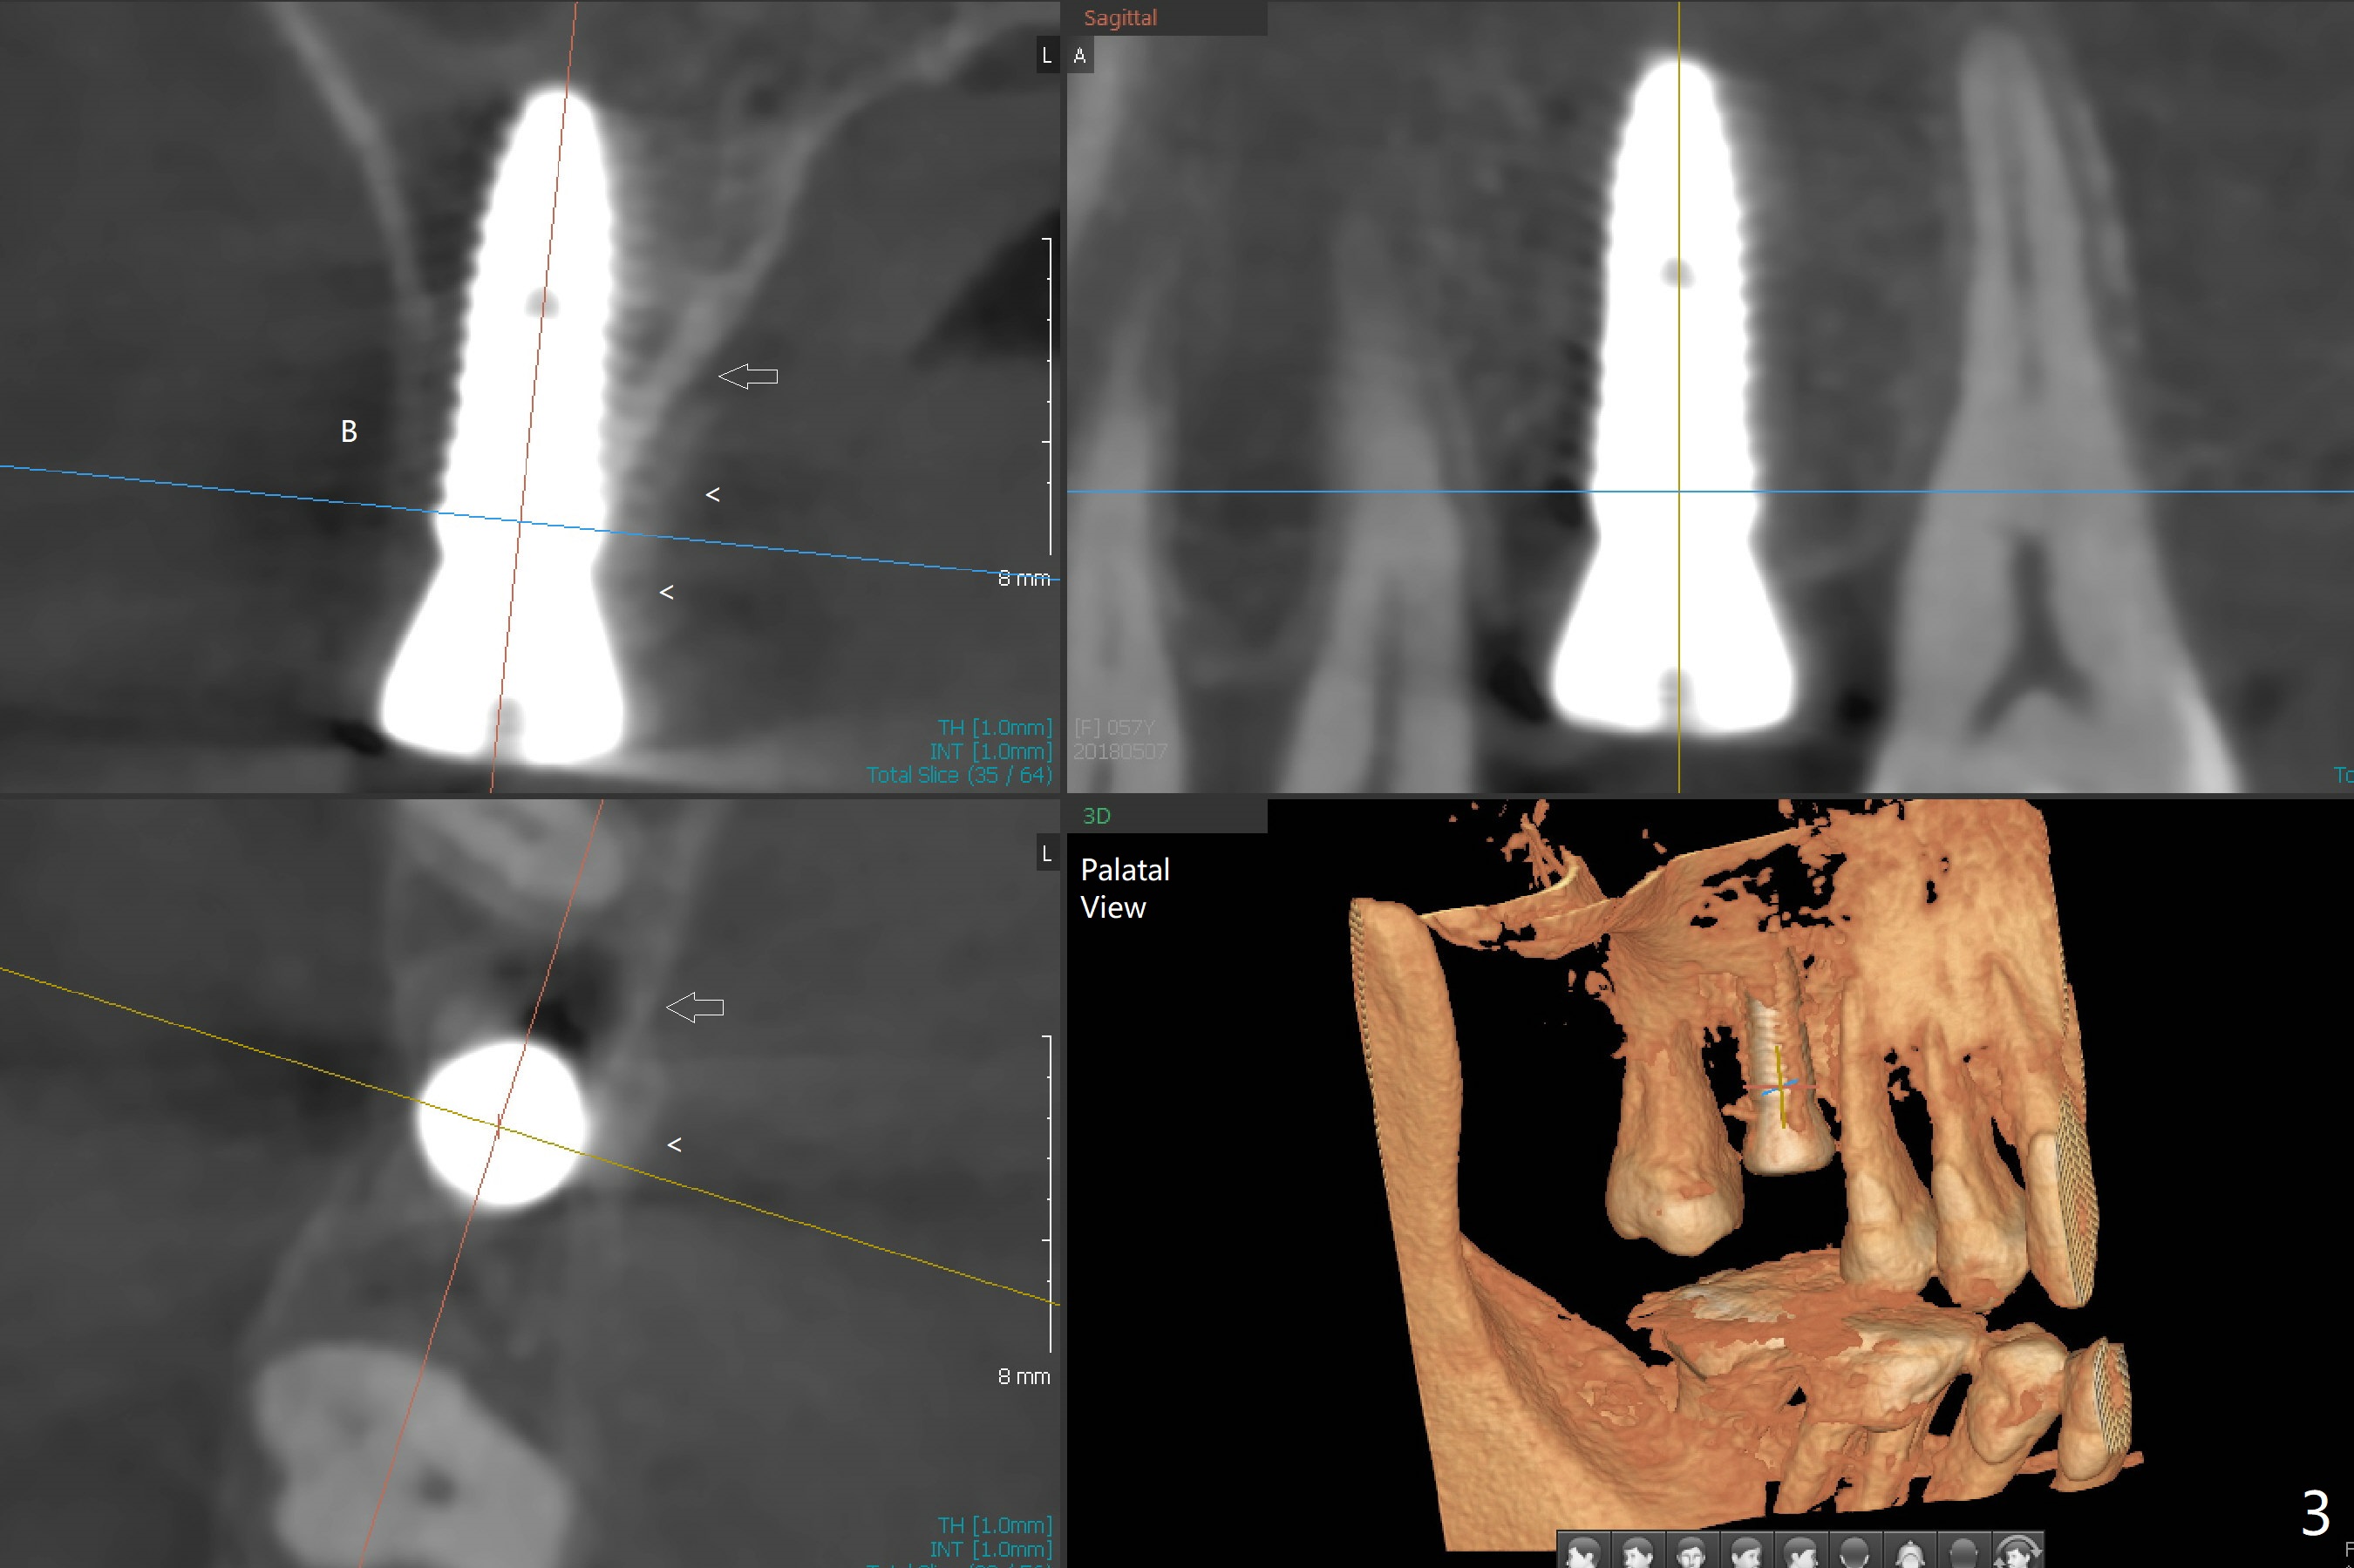

With understanding tissue punch and engagement of drill as much as possible into guide sleeve before pressing pedal, guided surgery is accomplished with confidence (Fig.1,2).  With undersized drilling, there is no thread exposure palatally, when a flap is raised.  Vanilla graft is placed, since it has been prepared before incision.  No membrane is used.  It appears that the palatal bone expands while the implant is being placed.  CBCT taken 10 days postop shows apparently the coronal end of the palatal plate (Fig.3 arrows) and bone graft (<).  Although postop pain is slightly more associated with incision for bone graft, the wound heals with periodontal dressing 10 days postop.